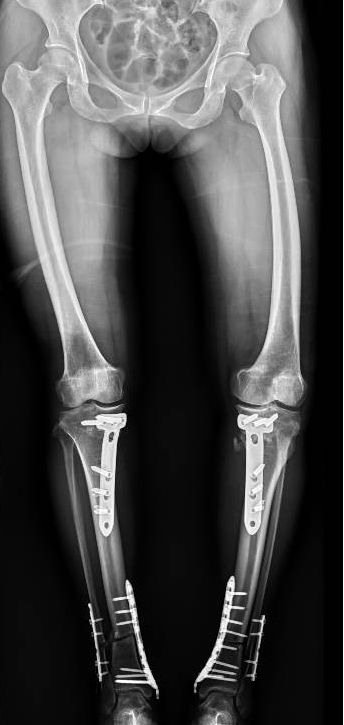

李彬在詳細了解了董阿姨的病史、進行了全面的體格檢查和相關(guān)的輔助檢查后,組織科室進行了深入的討論。最終的“答案”是——雙膝骨性關(guān)節(jié)炎、雙膝關(guān)節(jié)畸形、骨質(zhì)疏松以及雙膝半月板損傷。

面對這樣復雜且嚴重的病情,李彬并沒有退縮。他深知,對于董阿姨來說,這不僅僅是一次手術(shù),更是一次重生的機會。因此,他精心制定了手術(shù)方案:對雙下肢脛骨近端、遠端以及雙側(cè)腓骨遠端進行截骨矯形,并進行植骨內(nèi)固定。這樣的手術(shù)方案,無疑是對醫(yī)生技術(shù)的一次高難度挑戰(zhàn)!

手術(shù)前 手術(shù)后

手術(shù)很成功!經(jīng)過精心的治療和護理,董阿姨在9月順利出院。當她再次站在鏡前時,她驚喜地發(fā)現(xiàn)自己仿佛長高了一截,那份曾經(jīng)讓她備受折磨的疼痛與不適也逐漸消失了。